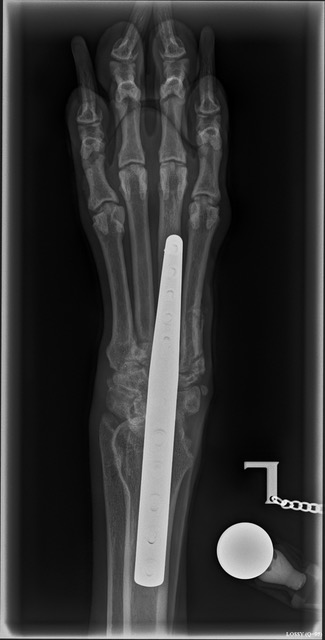

September 2021 - Unfortunately, Foxy had a traumatic accident on a walk, resulting in her totally rupturing the ligaments in her pastern (wrist) which are unrepairable, so she had to have surgery called a Pancarpal Arthrodesis to fuse the joints together and a plate put in her leg, culminating in an alteration to her gait and a low level permanent pain free lameness. (This injury is usually caused by either the dog running at speed and her leg going down a hole and then her twisting round, or by jumping from a great height and taking all the weight on her pasterns. In Foxy's case, it was likely to be the former.) She then spent 5 months in a crate with the level of exercise slowly increased until sufficient new bone had grown around the joints and after 5 months, she could start short off lead walks and thankfully is now back to her normal exercise levels. Obviously, this has now precluded her from being shown again which is extremely disappointing. However, Allan is hoping to continue to do some light Gundog work with her and hopefully enter some working tests.

The photos below show the metalwork in her leg but she lives a perfectly normal life and is back to her happy, outgoing self, which is the best possible outcome for our fabulous Foxy.